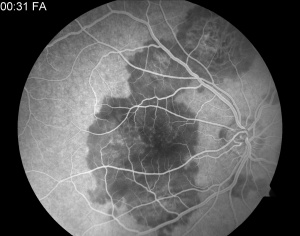

- Fluorescein angiography (FA): Active lesions exhibit early hypofluorescence (blockage) corresponding to the placoid lesions followed by late, irregular hyperfluorescent staining.[5] Early hypofluorescence may represent poor perfusion of the choriocapillaris or signal attenuation from overlying outer retina and/or RPE thickening. Late hyperfluorescence may be a result of vascular leakage, which resolves in subacute or healed lesions.[21]